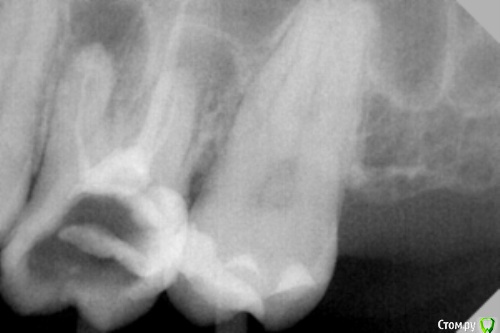

dr.Dre Опубликовано 5 сентября, 2016 Поделиться Опубликовано 5 сентября, 2016 Добрый день коллеги,26 зуб асимптоматический апикальный периодонтит,перелечивание.Мезиальный канал перфорнул,все время попадаю в перфорацию никак не могу зацепить корневой канал.Есть ли смыл в лечение такого зуба? Ссылка на комментарий

vse32 Опубликовано 5 сентября, 2016 Поделиться Опубликовано 5 сентября, 2016 Похоже Вы не мезиальный перфорнули, а сделали перфу на дне в бифуркацию. Мне кажется все еще реально пройти по каналу.Во всяком случае так по снимку видится. 1 Ссылка на комментарий